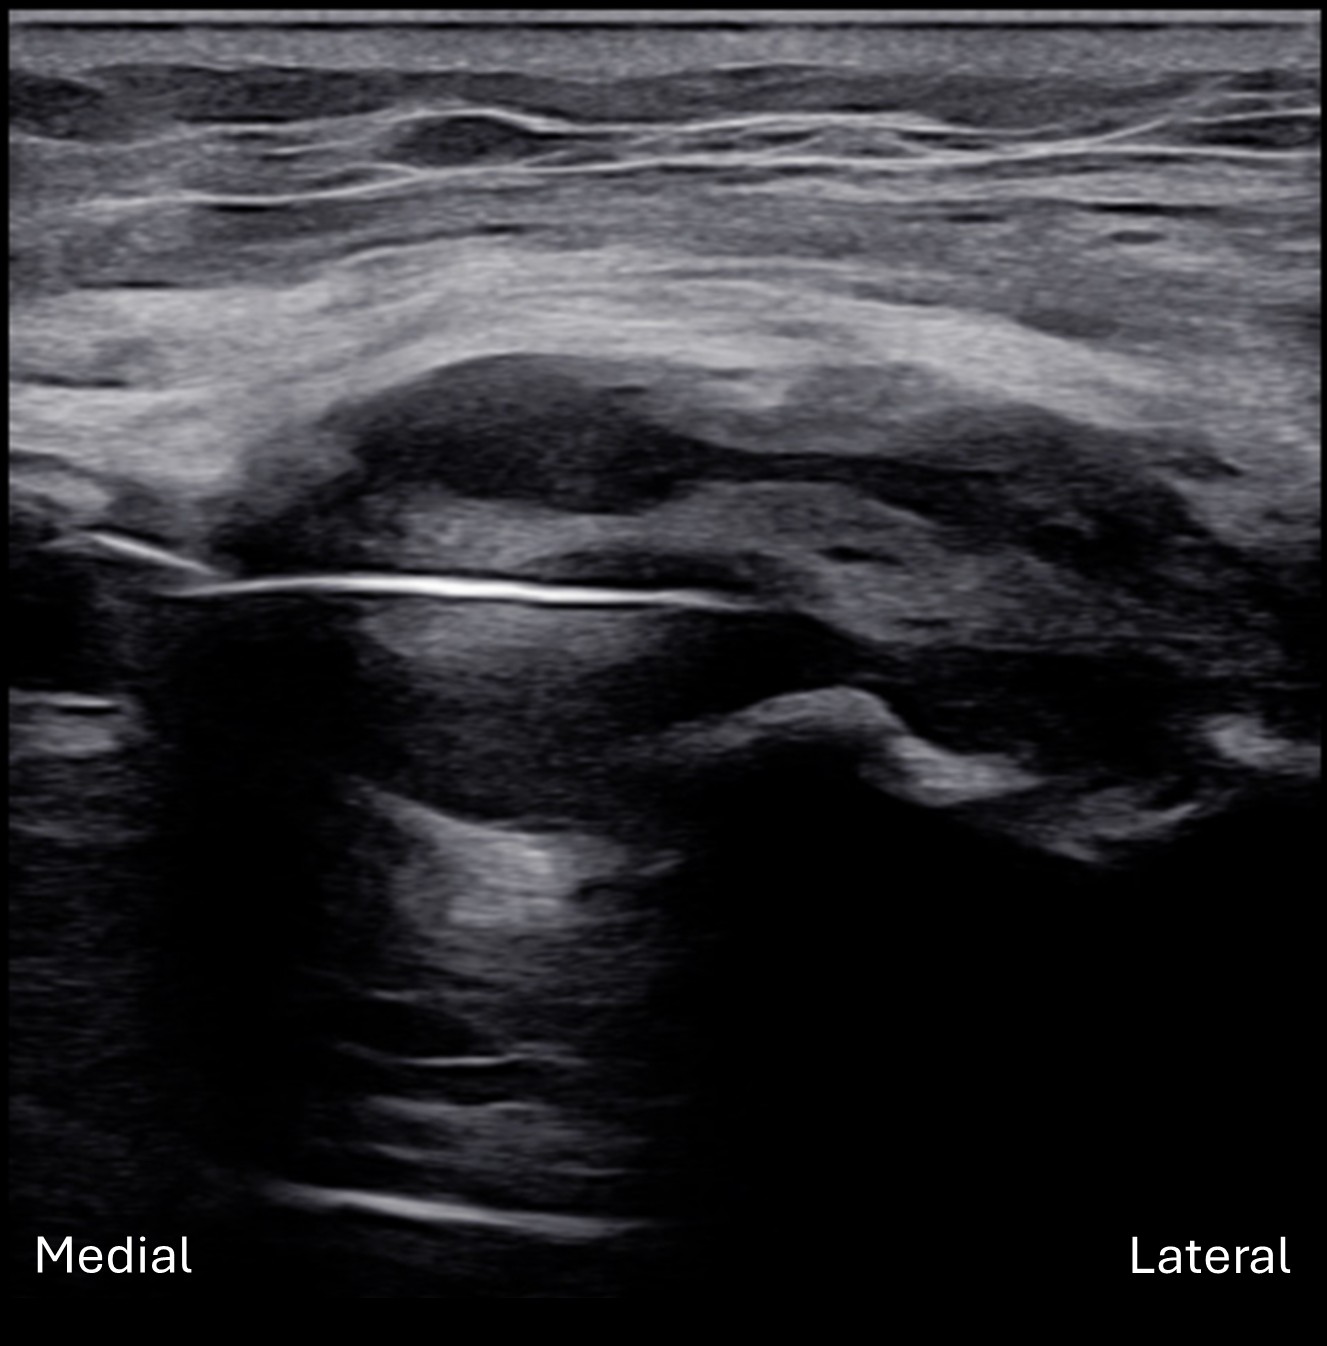

Unlabeled long axis view of the left posterior interosseous nerve (PIN) within the radial tunnel.